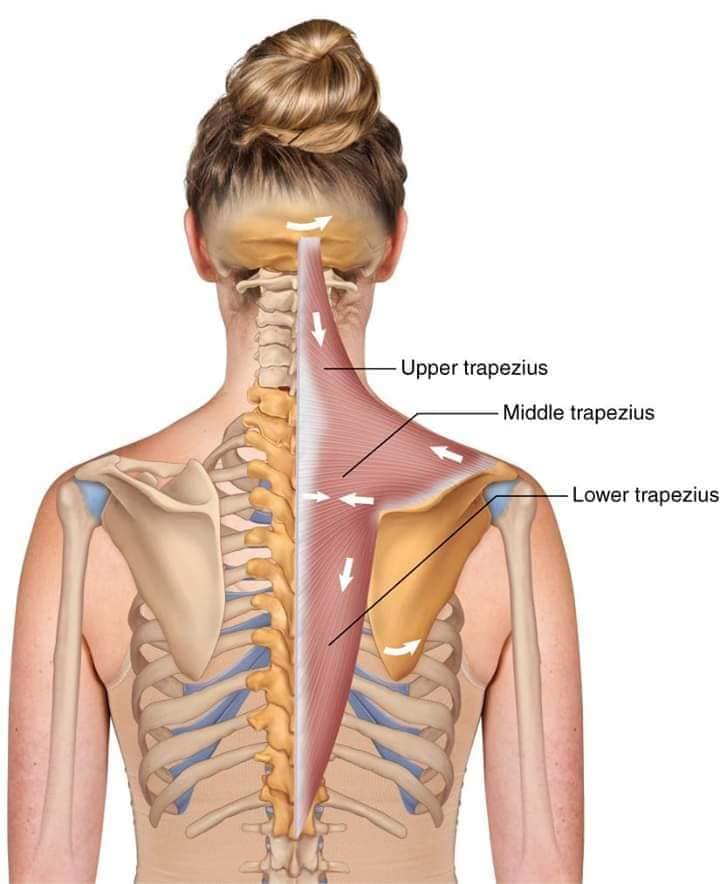

М'язи, що розширюють шию: М'язи, що розширюють шию: включають трапецієподібний м'яз, який бере участь у піднятті плечей і розширенні шиї.

М'язи, що піднімають лопатку: Трапецієподібний м'яз: великий м'яз, що покриває верхню частину спини. Його функція - підтримка і рух лопаток, а також забезпечення стабільності хребта.